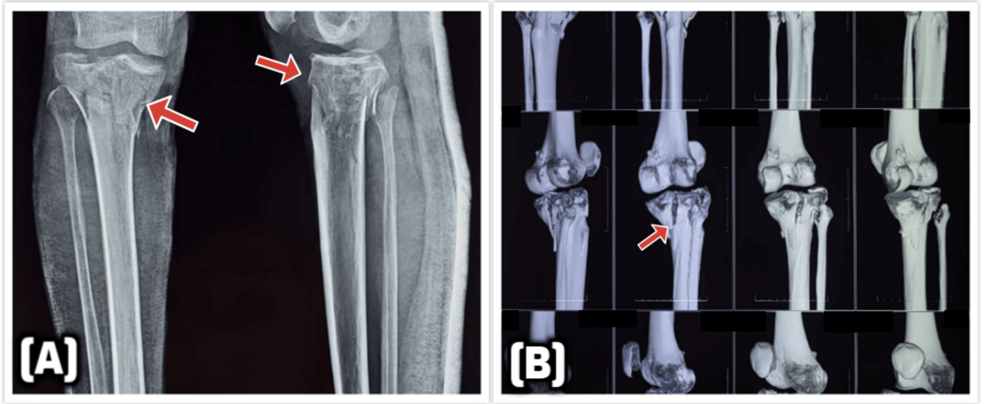

Influence of the fixation stability on the healing time–a numerical study of a patient-specific fracture healing process

Comparative analysis of tibial plateau fracture osteosynthesis: A finite element study